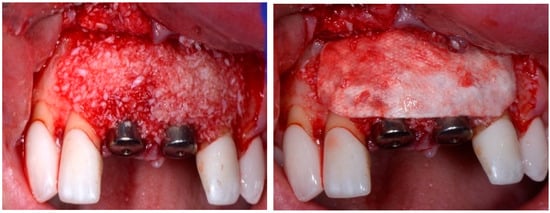

A 50-year-old female in good health and a non-smoker presented to our clinic with a failing maxillary left central incisor (Figure 13). The treatment plan consisted of the extraction of the existing tooth and replacing it with an implant. The preoperative surgical protocol described in patient 1 was followed. An L-shaped aesthetic flap design was used, revealing a buccal wall defect (Figure 14). The implant was placed with a screw-retained chair-side temporary crown (Figure 15), followed by the placement of bone graft material over the boney defect (Figure 16). A double-layer collagen membrane was placed and the flap closed. After six months, the final ceramic crown was inserted (Figure 17).

Figure 16.

Clinical view post grafting.